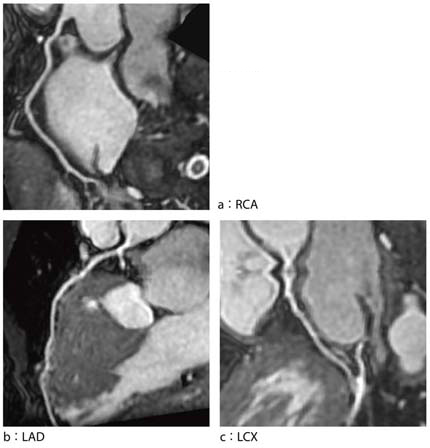

新しい心臓用Volumeアプリケーションである3D Heartでは,心筋信号を抑えるT2-prepパルスが追加されたほか,ペンシルビームを応用した新しい横隔膜同期やスライストラッキング等,さまざまな技術が搭載され,より精度の高い安定した冠動脈描出が可能となっている(図3,4,5)。また,心臓全体をマルチスラブ(5スラブ程度)で撮像することが可能となり,末梢血管の描出能も大きく向上している。

当院で3D Heartを使用したMRCAの成績は,トータル検査時間が平均20分,成功率が85%となっている。血管の描出に関しては右冠動脈,左前下行枝は,ほぼ全例で末梢まで描出され,従来評価困難であった左回旋枝でも,近位部で約9割,中間部,末梢血管でも約8割の描出が可能となっている。末梢の冠動脈病変の診断能が上がっており,今後,MRCAの使用頻度はさらに増えていくものと思われる。

図3 新しい横隔膜同期法やスライストラッキング技術, 図5 図3と同一症例のPWMIP像 |

図4 図3と同一症例のcurved MPR像 |